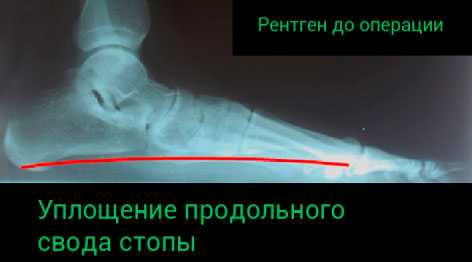

Рентгенографию. Этот метод обеспечивает нас изображениями плотных анатомических структур, например, костей. Он позволяет выявить в т.ч. дегенеративные изменения суставов. Если планируется оперативное лечение, то рентгенография позволяет выполнить необходимые измерения и выбрать наиболее оптимальную тактику оперативного лечения.

Рентгенограмма стопы в боковой проекции пациента с тяжелым плоскостопием. Данному пациенту в дополнение к перемещению сухожилия и остеотомии пяточной кости выполнен артродез среднего отдела стопы.

Определение патологии данного типа осуществляется, как визуально, так и по методике рентгена.